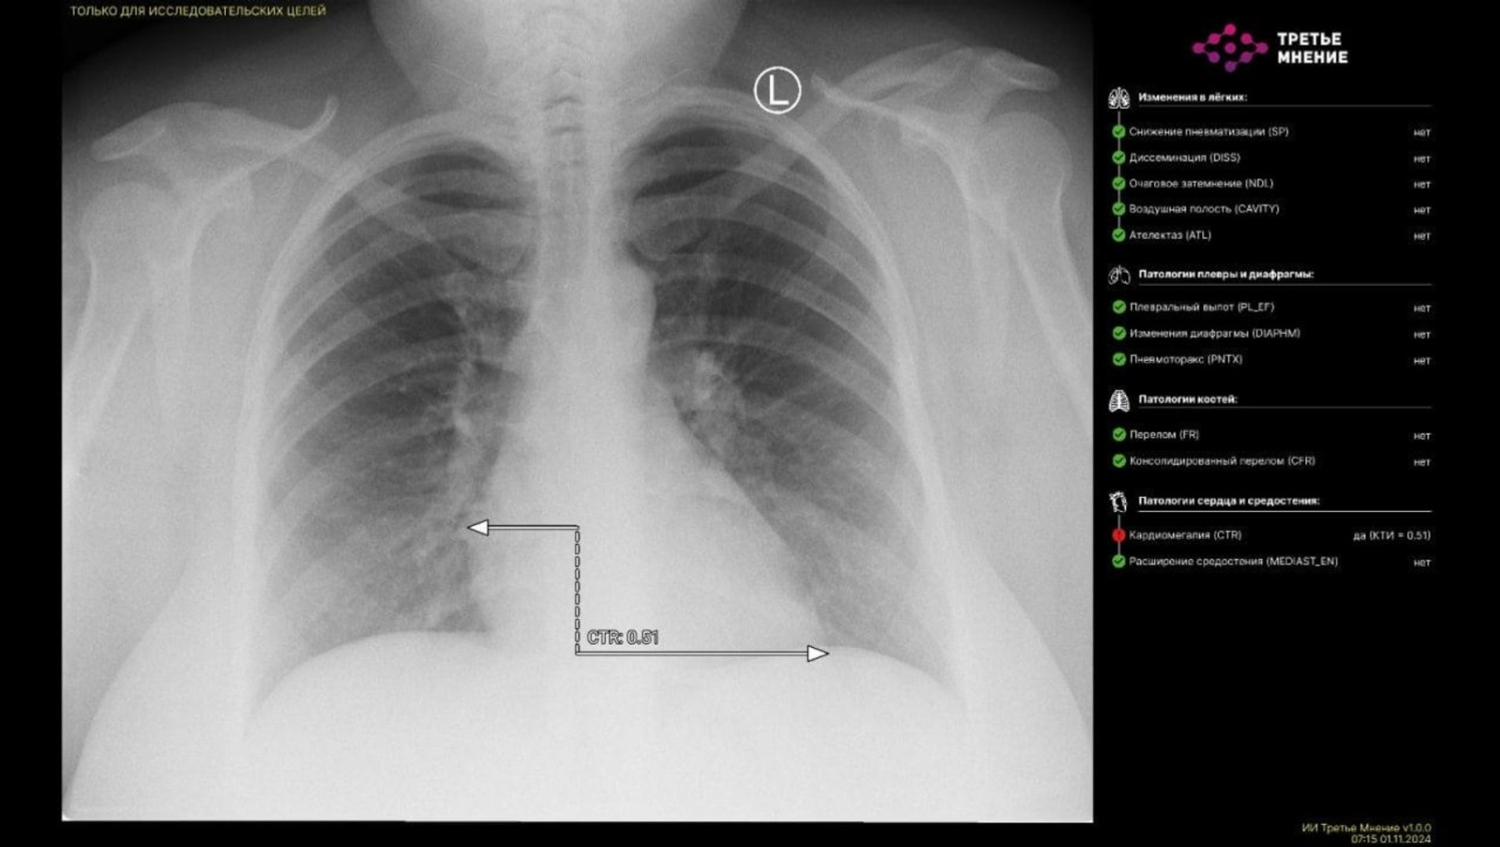

Настоящим технологическим прорывом в этом году стало и то, что впервые в Башкирии искусственный интеллект расшифровал рентгеновский снимок пациента. Специалисты городской больницы № 21 направили на специальную платформу «МосМедИИ» рентген органов грудной клетки пациента. Уже через минуту цифровой помощник выдал результат: провел интерпретацию полученного медицинского изображения, разметил зоны патологических очагов и составил протокол исследования.

«Это большой прорыв в области цифровизации здравоохранения. ИИ поможет оперативнее читать КТ, МРТ, рентген-снимки, флюорографию, ангиографию — все то, что сохраняется в "картинке". Стоит отметить, что последнее слово все же будет оставаться за врачом. Все работы проводятся в рамках национального проекта "Здравоохранение"», — отмечал министр здравоохранения РБ Айрат Рахматуллин.